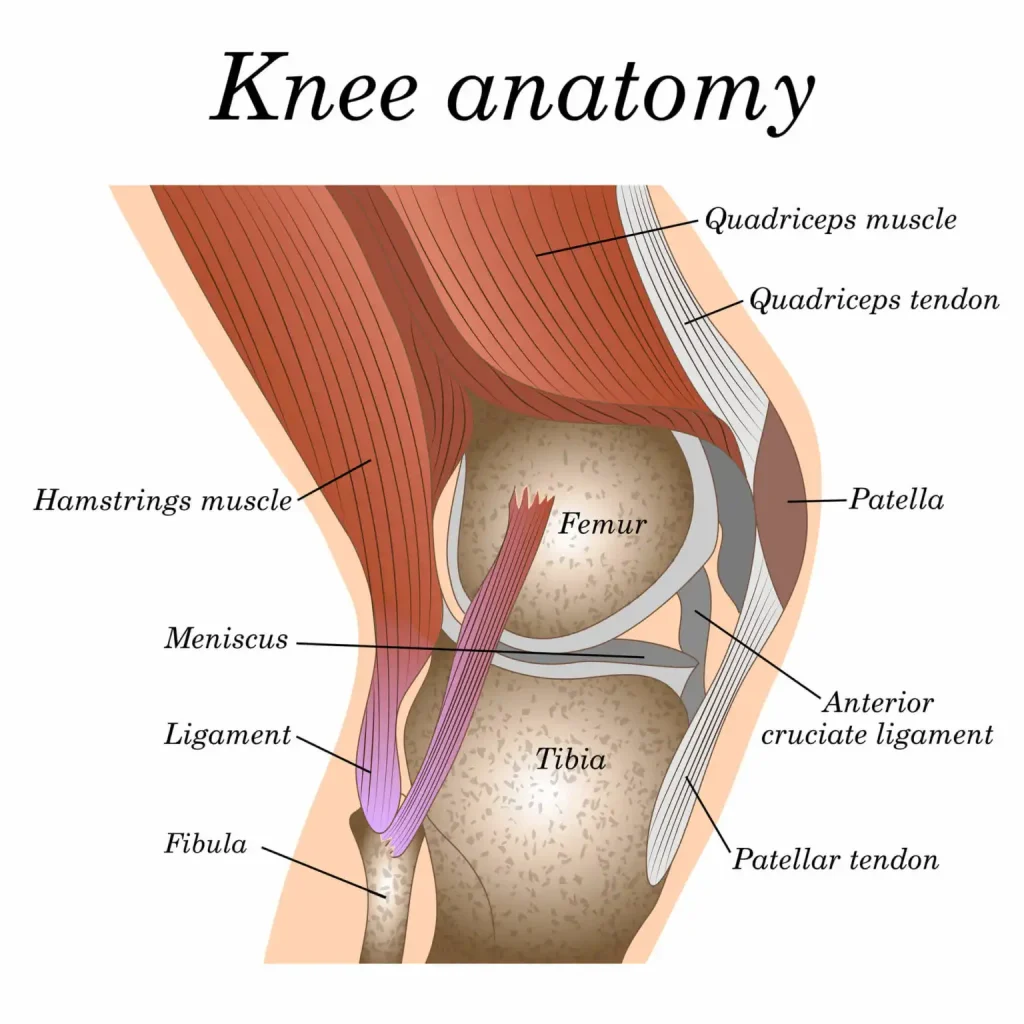

اگر زانوی شما بر اثر آرتروز یا آسیبدیدگی شدید، درد مداوم دارد و حرکات آن محدود شده، احتمالاً به پروتز زانو نیاز دارید تا کیفیت زندگیتان به حالت عادی بازگردد.جهت کسب مشاوره رایگان با ما تماس حاصل فرمایید. 📞 همین حالا میتوانید از یکی از 3 روش زیر برای مشاوره رایگان و فوق تخصصی و کاملا […]

در سال ۱۴۰۴، پیشرفتهای پزشکی امید تازهای برای درمان دردهای مزمن زانو ایجاد کردهاند. پروتز مفصل زانو آمریکایی با بهرهگیری از فناوریهای نوین، طراحی دقیق و دوام بالا، به یکی از گزینههای برتر در جراحی تعویض مفصل زانو تبدیل شده است. این پروتزها با هدف کاهش درد، بهبود حرکت و بازگشت سریعتر به زندگی روزمره […]

انتخاب برند مناسب برای پروتز مفصل زانو، نقش کلیدی در دوام، راحتی و موفقیت جراحی دارد. آشنایی با بهترین مارکهای جهانی، تصمیمگیری را برای بیمار و جراح آسانتر میکند.جهت کسب مشاوره رایگان سامان ارتوپد با شماره 09106063586 تماس حاصل فرمایید. بهترین مارک پروتز مفصل زانو؛ انتخاب حرفهای برای عمر بیشتر مفصل مصنوعی✔ کدام برند پروتز […]

این مقاله توسط واحد تولید محتوای گروه ارتوپدی سامان، بزرگترین وبسایت ارتوپدی در ایران، تهیه شده است. آسیب غضروف زانو یک مشکل شایع در بین افراد، به ویژه افراد مسن و ورزشکاران است. غضروف بافتی نرم و لغزنده است که از استخوان ها در مفصل زانو محافظت می کند و حرکتی روان را تضمین می […]